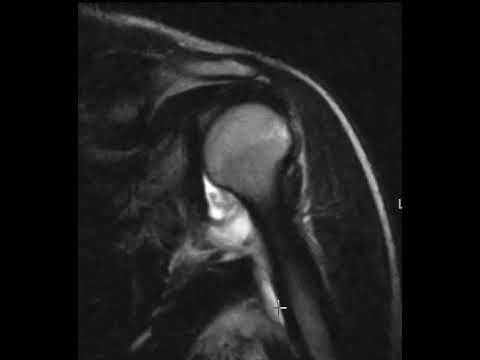

Inferior shoulder dislocation with HAGL lesion on MRI

HAGL Lesion: Diagnosis, Risks, and Advanced Imaging Techniques; HAGL 병변: 진단, 주의점과 진보된 영상 진단 기술

Shoulder Instability MRI: Part V Macroinstability Injuries

Shoulder MRI: Instability, Part VI

MRI IN SHOULDER INSTABILITY | MALINI LAWANDE | Hill Sachs | Bankart | Labral Tear | ALPSA | HAGL